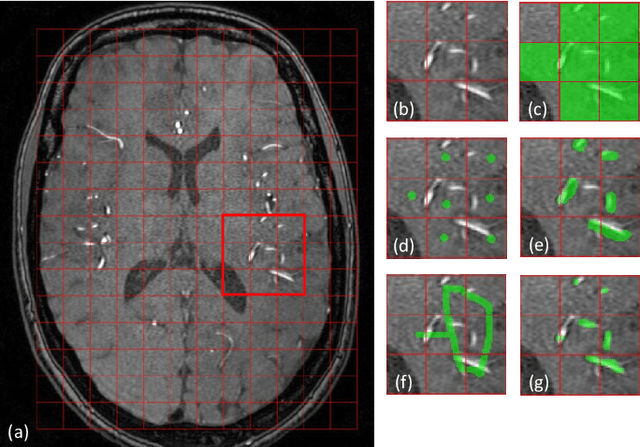

Abstract:The use of deep learning techniques for 3D brain vessel image segmentation has not been as widespread as for the segmentation of other organs and tissues. This can be explained by two factors. First, deep learning techniques tend to show poor performances at the segmentation of relatively small objects compared to the size of the full image. Second, due to the complexity of vascular trees and the small size of vessels, it is challenging to obtain the amount of annotated training data typically needed by deep learning methods. To address these problems, we propose a novel annotation-efficient deep learning vessel segmentation framework. The framework avoids pixel-wise annotations, only requiring patch-level labels to discriminate between vessel and non-vessel 2D patches in the training set, in a setup similar to the CAPTCHAs used to differentiate humans from bots in web applications. The user-provided annotations are used for two tasks: 1) to automatically generate pixel-wise labels for vessels and background in each patch, which are used to train a segmentation network, and 2) to train a classifier network. The classifier network allows to generate additional weak patch labels, further reducing the annotation burden, and it acts as a noise filter for poor quality images. We use this framework for the segmentation of the cerebrovascular tree in Time-of-Flight angiography (TOF) and Susceptibility-Weighted Images (SWI). The results show that the framework achieves state-of-the-art accuracy, while reducing the annotation time by up to 80% with respect to learning-based segmentation methods using pixel-wise labels for training